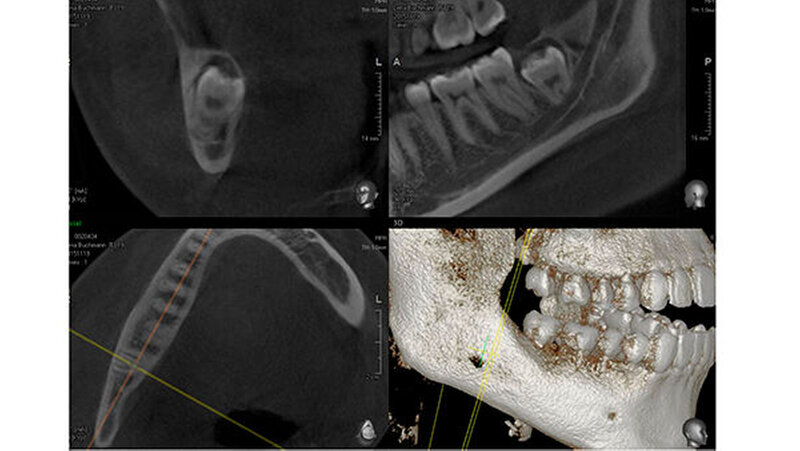

Aufgrund der engen Lagebeziehung der Weisheitszähne 38 und 48 zum Nervus alveolaris inferior (Abbildung 1) wurde zur weiterführenden Diagnostik eine digitale Volumentomografie (DVT) in der Praxis von Dr. Burkard Langenfeld in Friedrichshafen durchgeführt (Abbildungen 2 und 3).

Auf der DVT-Aufnahme zeigte sich vor allem in regio 48 der extrem Nerv-nahe Bezug und eine sehr tief impaktierte Lage des Zahns zum Ramus. Aufgrund dieser Befunde wurde eine Verplattung wegen der möglichen iatrogenen Bruchgefahr des Unterkiefers zur Stabilisierung des Unterkiefers mit der Patientin präoperativ besprochen.

Die Zähne 28 und 18 wurden nach Aufklappung und Osteotomie schonend entfernt. Eine Mund-Antrum-Verbindung konnte intraoperativ ausgeschlossen werden. Für regio 48 wurde eine sulkuläre Schnittführung ab regio 43 gewählt, da eine eventuelle Verplattung vorgesehen war. Intraoperativ ließ sich der Zahn 48 komplikationslos in toto entfernen und die Alveole war klinisch knöchern intakt, der Nerv nicht verletzt (Abbildung 4).